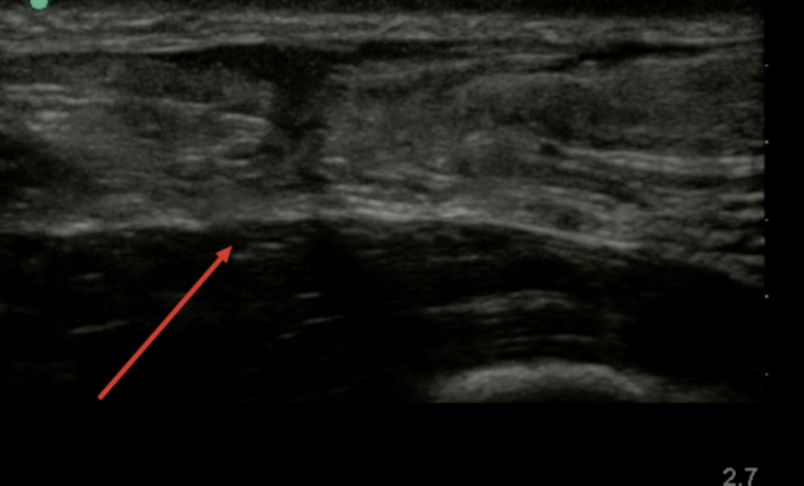

USG esg

A

UTILIDAD LIMITADA

PERMITE EVALUAR ATFL

US RTAQ

Excelente metodo

tendon engrosado e hipoecoico: tendinopatía

distinguir entre desgarro total y parcial